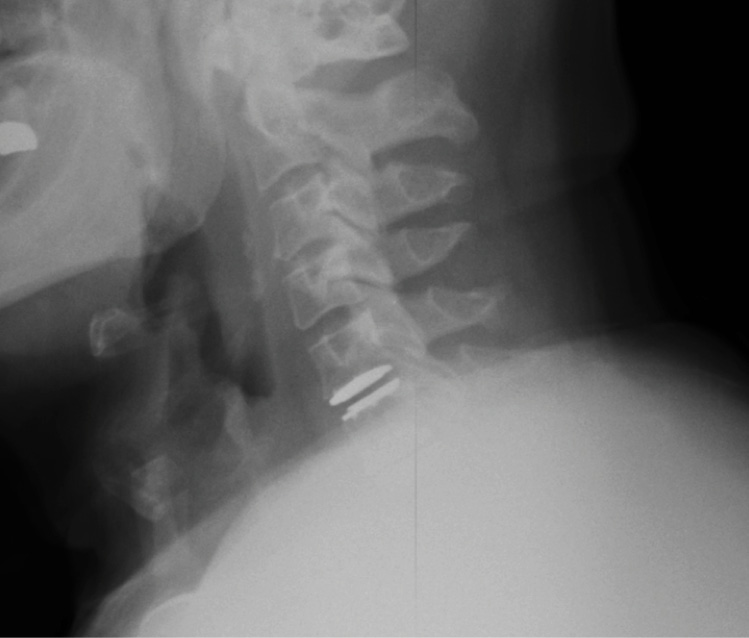

Pre-op dynamic radiographs demonstrate partial loss of disc height at C5-6 and C6-7 without instability or scoliosis.